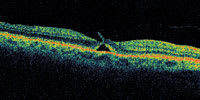

| Figure 2. There is subretinal fluid beginning to form under the central fovea in what may represent a prehole condition. No full-thickness defect can be observed in any cut. |

A central clinical challenge has been accurately diagnosing early macular holes which may be mimicked by many other conditions.34,35 No imaging modality has enhanced our diagnostic capability more than the OCT; superior imaging capabilities have improved diagnostic accuracy, clinical monitoring, and postoperative assessment.36-38 The OCT unequivocally demonstrates early stages of full-thickness macular holes (Figure 1), and allows distinction of pseudohole and pre-macular hole conditions in almost all instances. Fluid accumulation in early, presumed pre-macular hole stages have been corroborated by OCT observations (Figure 2). Serial images have been reported showing the progression from apparent impending macular holes to full thickness macular holes.39-42 It has depicted many other configurations that might be in the spectrum of lamellar or pre-macular hole conditions (Figure 3 and 4).